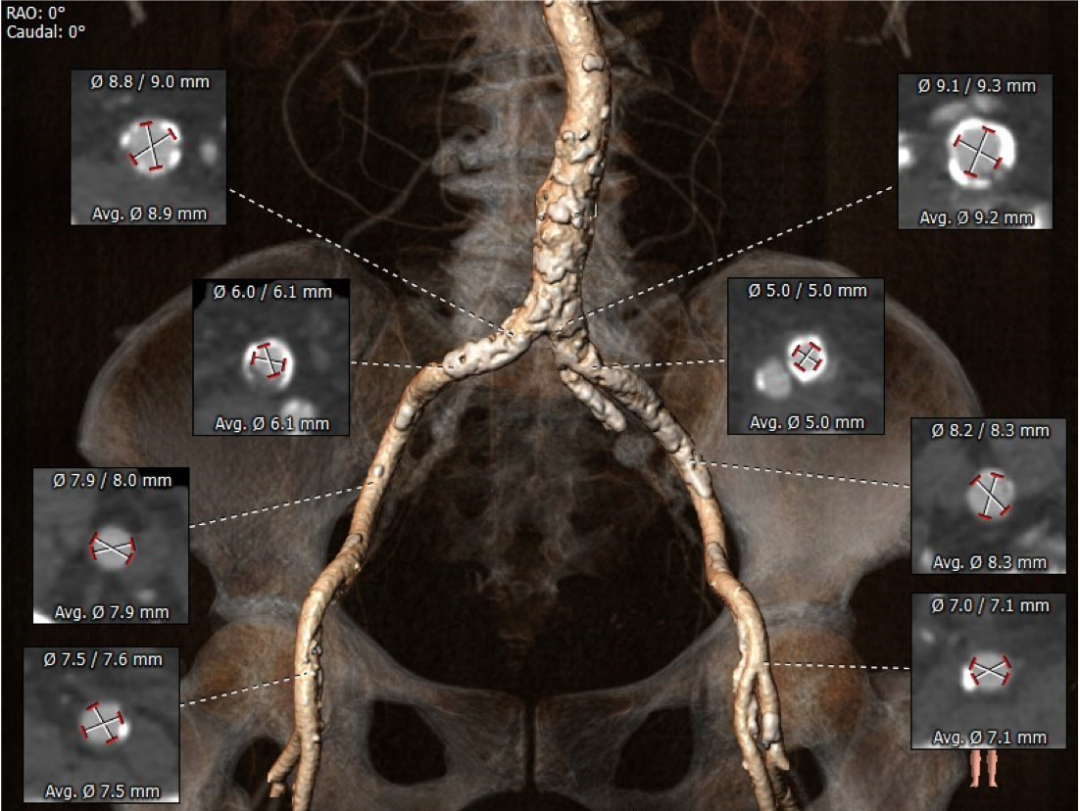

血管外周入路评估

腹主下段、双髂总附近多发钙化,部分截段钙化呈环状分布,血管内径受限,双侧股动脉穿刺点周围少量附壁钙化。